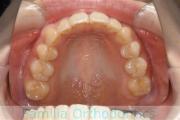

- ≫治療前

上顎

下顎

- ≫治療中 ステップ1